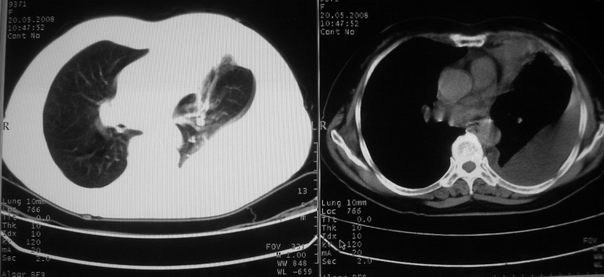

以下是引用w_jianhua在2008-5-22 12:59:00的发言:[br]1.左肺上叶肺癌并左侧胸腔积液可能性大。2不除外支气管内膜结核并包裹性胸腔积液,建议支气管镜检3.左肺下叶肺大泡,肺气肿